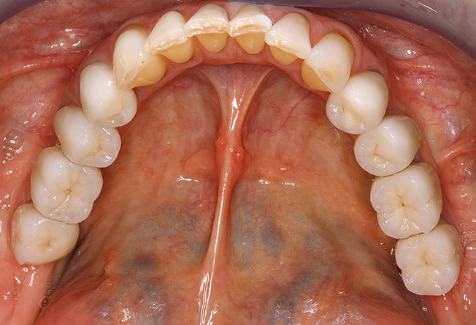

Aufgrund der bestehenden parodontalen Vorerkrankung erfolgte die unterstützende Parodontaltherapie (UPT) in den ersten Jahren in einem Drei­Monats­Intervall. Dabei zeigte die Patientin eine hohe Motivation und gute Compliance. Bei den jährlich erhobenen Sondierungsbefunden zeigten sich stabile parodontale Verhältnisse mit einem BOP­Index unter fünf Prozent. Aufgrund der stabilen parodontalen Situation und der guten Mitarbeit der Patientin wurde ab dem sechsten Jahr der prothetischen Funktionsphase das Recallintervall auf halbjährlich um­gestellt. Auch mit diesem veränderten Recallintervall zeigten sich bei der jeweils jährlichen Aufnahme des Parodontalstatus stabile parodontale Verhältnisse, ohne Zunahme der Sondierungstiefen und einem BOP­Index unter fünf Prozent (Abb. 2a und b).

Das aktuelle Arbeitskonzept für die UPT

Die Aktualisierung der Anamnese stellt im Rahmen der UPT eine zentrale Maßnahme dar, sie sollte mindestens einmal jährlich erfolgen. Sie dient dazu, mögliche neue Risikofaktoren zu erkennen und zu dokumentieren. Vor allem dann, wenn ein Patient langjährig betreut wird, ist es wichtig, zu erfahren, ob sich patientenspezifische und allgemeinmedizinische Risikofaktoren verändert haben. Hier sollte an erster Stelle an ein erhöhtes Risiko durch Diabetes gedacht werden, aber auch andere allgemeinmedizinische Erkrankungen (kardiovaskuläre Erkrankungen und Neoplasien) können aufgrund der erfolgten Therapien und der notwendigen Medikamenteneinnahme zu einem veränderten Risikoprofil führen. Das Update der Anamnese ist also auch im Rahmen der UPT sehr wichtig, um gegebenenfalls aufgrund eines veränderten Risikoprofils eine Veränderung des Behandlungsintervalls zu veranlassen. Im nächsten Schritt ist es wichtig, der Diagnostik besondere Aufmerksamkeit zu schenken. Die Instrumentation ist zwar ein zentraler Bestandteil der UPT, in keinem Fall sollte sie aber Bestandsaufnahme und Dokumentation verdrängen. Für die Diagnose ist dabei der parodontale Befund unerlässlich, eine Zunahme der Sondierungstiefen und eine Erhöhung des BOP­Index sind zentrale Indikatoren für eine Progression parodontaler und periimplantärer Erkrankungen. Zum Erheben der benötigten Daten darf daher nicht davor zurückgeschreckt werden, auch Implantate zu sondieren. Dabei ist es wichtig, dass hierfür millimeterskalierte PAR­Sonden verwendet werden. Für die Sondierungsbefunde an natürlichen Zähnen haben sich seit Jahrzehnten metallische Sonden bewährt. Bei Implantaten ist die Herausforderung für das Erheben korrekter und reproduzierbarer Sondierungsbefunde größer. Da es durch die Diskrepanz von Implantatdurchmesser und Kontur der Suprakonstruktion regelmäßig zu einer Überkonturierung der Suprastruktur kommt, sind für Sondierungen an Implantaten flexible, aber dennoch millimeterskalierte Son­ den sehr sinnvoll (z. B. Colorvue Kit PCV11KIT6, Hu­Friedy; Abb. 4).